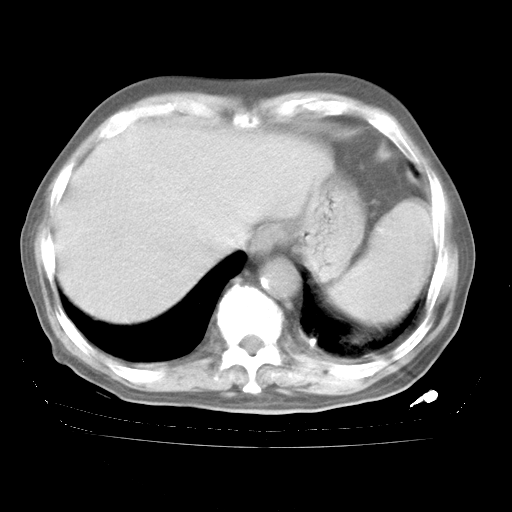

腹部B超:胆囊壁增厚,肝、胆、胰、脾、肾无异常,肠系膜淋巴结、腹膜后淋巴结无增大。